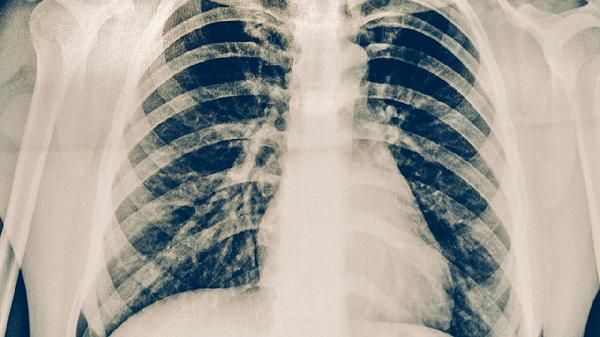

支原體肺炎多久能恢復(fù)抵抗力了呢

支原體肺炎患者恢復(fù)抵抗力一般需要2-4周,實(shí)際時(shí)間與感染嚴(yán)重程度、基礎(chǔ)健康狀況、營(yíng)養(yǎng)支持、治療規(guī)范性和休息充分性等因素相關(guān)。

輕癥患者呼吸道黏膜損傷較輕,免疫細(xì)胞再生速度較快,通常2周內(nèi)可恢復(fù)免疫功能;中重度感染可能引發(fā)持續(xù)性炎癥反應(yīng),需3-4周才能重建免疫屏障。合并肺外并發(fā)癥者恢復(fù)期可能延長(zhǎng)。